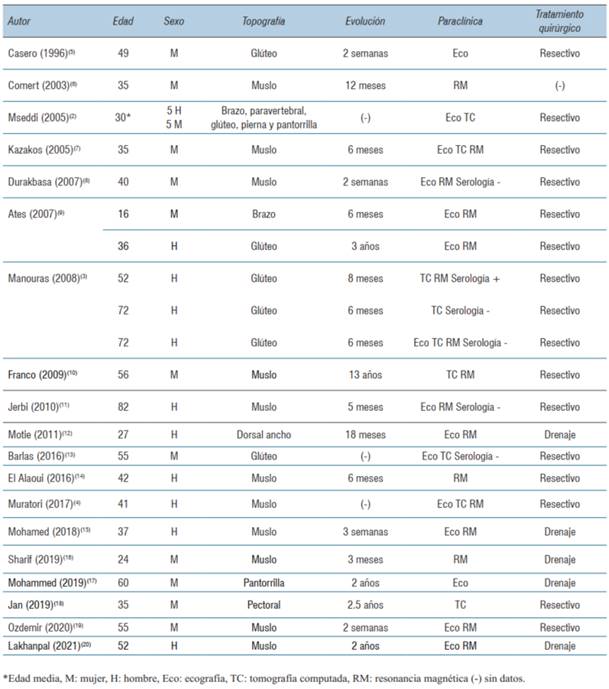

Este trabajo se realizó siguiendo las guías SCARE 2020. Se realizó una búsqueda bibliográfica en las bases de datos PubMed y LILACS. Los términos de búsqueda utilizados fueron: (“hydatid disease” [All Fields]) AND (“muscle” [All Fields]). Fueron incluidos artículos en idioma español, inglés, portugués y francés. Fueron excluidos trabajos realizados en la población pediátrica y que incluían quistes hidáticos o pulmonares sincrónicos. La revisión bibliográfica se resume en la (tabla 1).

La actividad comercial ganadera del Uruguay explica la importante e histórica incidencia de hidatidosis en relación a otros países. En la década de 1990 se trataba de un país hiperendémico con una incidencia de 17,1/100.000 habitantes en uno de los primeros trabajos publicados por Purriel5,6. Actualmente, con la implementación de campañas de screening y control de la enfermedad, esta ha disminuido notoriamente a menos de la mitad7. El perfil epidemiológico predomina en el noroeste del país. De la revisión de casos clínicos se trató de pacientes todos procedentes de zonas endémicas, de edad media 45 años, con un rango entre los 16 a 82 años. La distribución por sexo fue 12 mujeres a 11 hombres.

La equinococosis quística músculo-esquelética es poco frecuente, dada la eficacia del filtro hepático y pulmonar que evita la migración del embrión hexacanto a la circulación sistémica2. Asimismo, el músculo esquelético no es un ambiente favorable para el desarrollo del embrión, dada la permanente contractilidad muscular y la producción de ácido láctico8. La topografía más frecuente fueron los grupos musculares del muslo, como en el caso presentado. Otras localizaciones fueron región glútea, tronco y brazo. La rica vascularización de estos grupos musculares constituye la puerta de entrada del parásito2,8.

La presentación clínica más frecuente fue la presencia de una tumoración de partes blandas de crecimiento progresivo, 20 meses en promedio con un rango de entre 2 semanas a 13 años. En la mayoría de los casos presentaron dolor, en ausencia de cambios en la piel o elementos fluxivos. Los autores concuerdan que los quistes hidáticos músculo-esqueléticos cursan de forma asintomática hasta que el tamaño del quiste se hace clínicamente evidente, o por la presencia de dolor, que se explicaría por la compresión de troncos nerviosos adyacentes3. En el caso presentado la paciente consultó por dolor y drenaje espontáneo, tratándose de una complicación evolutiva. Otras complicaciones descritas en esta topografía son la anafilaxia local y/o sistémica1.

La imagenología constituye un pilar diagnóstico fundamental, destacándose el uso de la ecografía, tomografía computada (TC) y RM (68% vs. 32% vs. 72%). De la revisión, en más de la mitad de los pacientes (n=15, 60%) se solicitaron dos estudios de imagen complementarios. La RM fue el estudio más solicitado, formando parte del algoritmo diagnóstico de las tumoraciones de partes blandas. Permite determinar el tamaño del quiste, y fundamentalmente sus relaciones musculares, vasculares y nerviosas, siendo una herramienta clave a la hora de planificar abordaje y táctica quirúrgica8,9. El quiste hidático se visualiza como una lesión quística cuya pared es hipointensa en comparación con el líquido intraquístico en secuencia T1. Es frecuente el hallazgo de vesículas prolígeras en su interior, como se observa en las (figura 1) y (figura2), que en T1 son hipointensas respecto a la matriz del quiste9. Se ha descrito en esta topografía la presencia del signo del camalote (water-lily sign), clásicamente comentado para quistes hepáticos o pulmonares. Puede verse edema perilesional por compresión o reacción inflamatoria de los tejidos adyacentes10. En todos los pacientes se asoció una ecografía de abdomen y/o tomografía de tórax y abdomen a fin de descartar enfermedad hepática o pulmonar sincrónica.